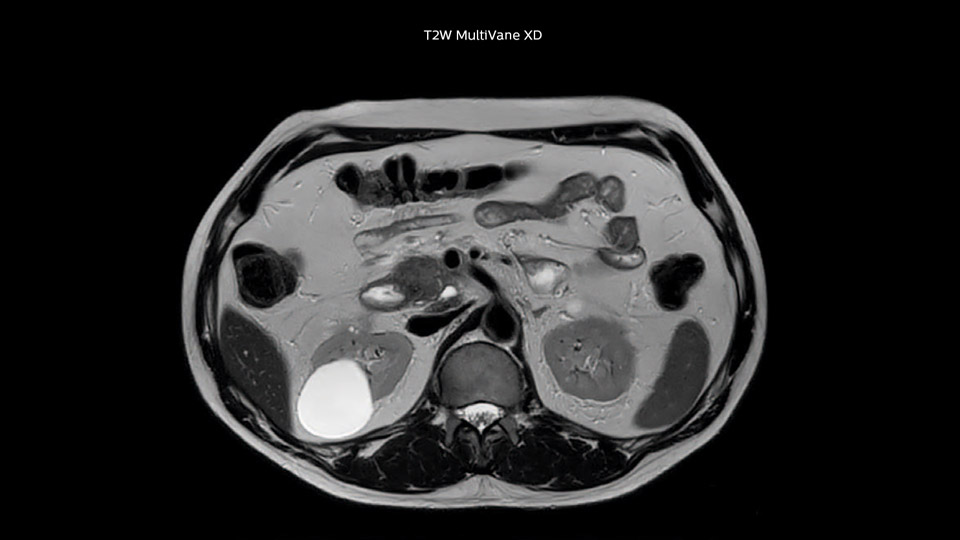

“With MultiVane XD we get excellent motion-corrected images with high spatial resolution. We typically first optimize our scan for high image quality, and when satisfied with that, we try to reduce the scan time. So, we combined MultiVane XD with dS SENSE, which allows us to shorten the scan time,” he explains. “The performance of MultiVane XD in liver imaging is outstanding. MultiVane XD with dS SENSE is a powerful development in improving liver image quality.”

“As we use breathhold imaging for T2-weighted liver scans, we depend on the patient’s ability to cooperate with the exam.

This can present a real challenge when we are looking for small lesions, such as in our oncological patients. However, with MultiVane XD motion correction, we get excellent images. This is important for our surgeons, because they want to know exactly where the lesions are.”

Comparison of liver MRI with and without MultiVane XD motion correction

In this example the image quality of the MultiVane XD images is evidently better than in the images without MultiVane XD. Ingenia 1.5T with dS Torso coil solution.

“We acquire one transversal high resolution T2-weighted sequence with 3 mm slice thickness, for example for pancreas or liver lesions. Then we also add a T2 fat suppressed MultiVane XD SPIR sequence. We perform these two routinely in our liver imaging. We use high dS SENSE factors to significantly shorten scan times to 2-4 minutes, which can improve our protocol; it’s a very robust scan.”

“I would absolutely recommend to other sites to implement MultiVane XD with dS SENSE in their abdominal cases, as it’s brilliant for robust, motion-corrected abdominal imaging. It provides us with excellent image quality with high resolution in a short time,” says Dr. Baumann. “I would advise using MultiVane XD for T2 and T2 fat suppressed high quality imaging for almost every liver case.”